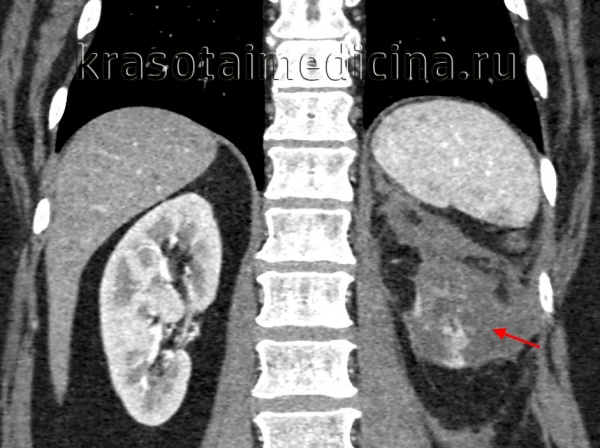

КТ ОБП/ЗП. Гнойное расплавление левой почки с формированием «мешка», заполненного гноем, с воспалительными изменениями прилежащей клетчатки.

- Рентгенодиагностика. При обзорной урографии на рентгенограмме видна тень увеличенной почки с четкими контурами. Часто обнаруживаются камни в почечной лоханке или мочеточнике, создающие механическую преграду для оттока гноя. Дополнительно используется ангиография почечных сосудов, оценивающая уровень кровоснабжения органа. КТ почек также определяет очаг, но позволяет отличить полость, заполненную гноем, от опухоли или кисты.

- УЗИ почек. Помогает локализовать воспалительный очаг, определить его форму, оценить качество уродинамики в лоханках и мочеточниках.